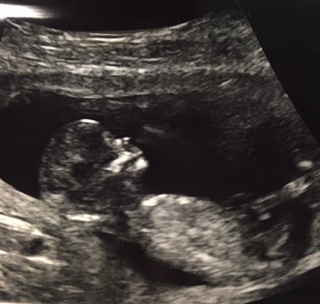

Hi - I'm new here! These were taken 12 weeks 4 days. I know there isn't a great view of the nu, baby was moving around a lot during the ultrasound. Please let me know your thoughts!

Attachment 32664Attachment 32665

Yeah, your wiggle worm didn't want to reveal it's goods just yet. Can't see the entire nub unfortunately ...

Oh, silly baby!! My anatomy scan is on 9/28 so I guess I'll have to wait until then. I know it's probably not as reliable but what about any skull theory predictions? :think: